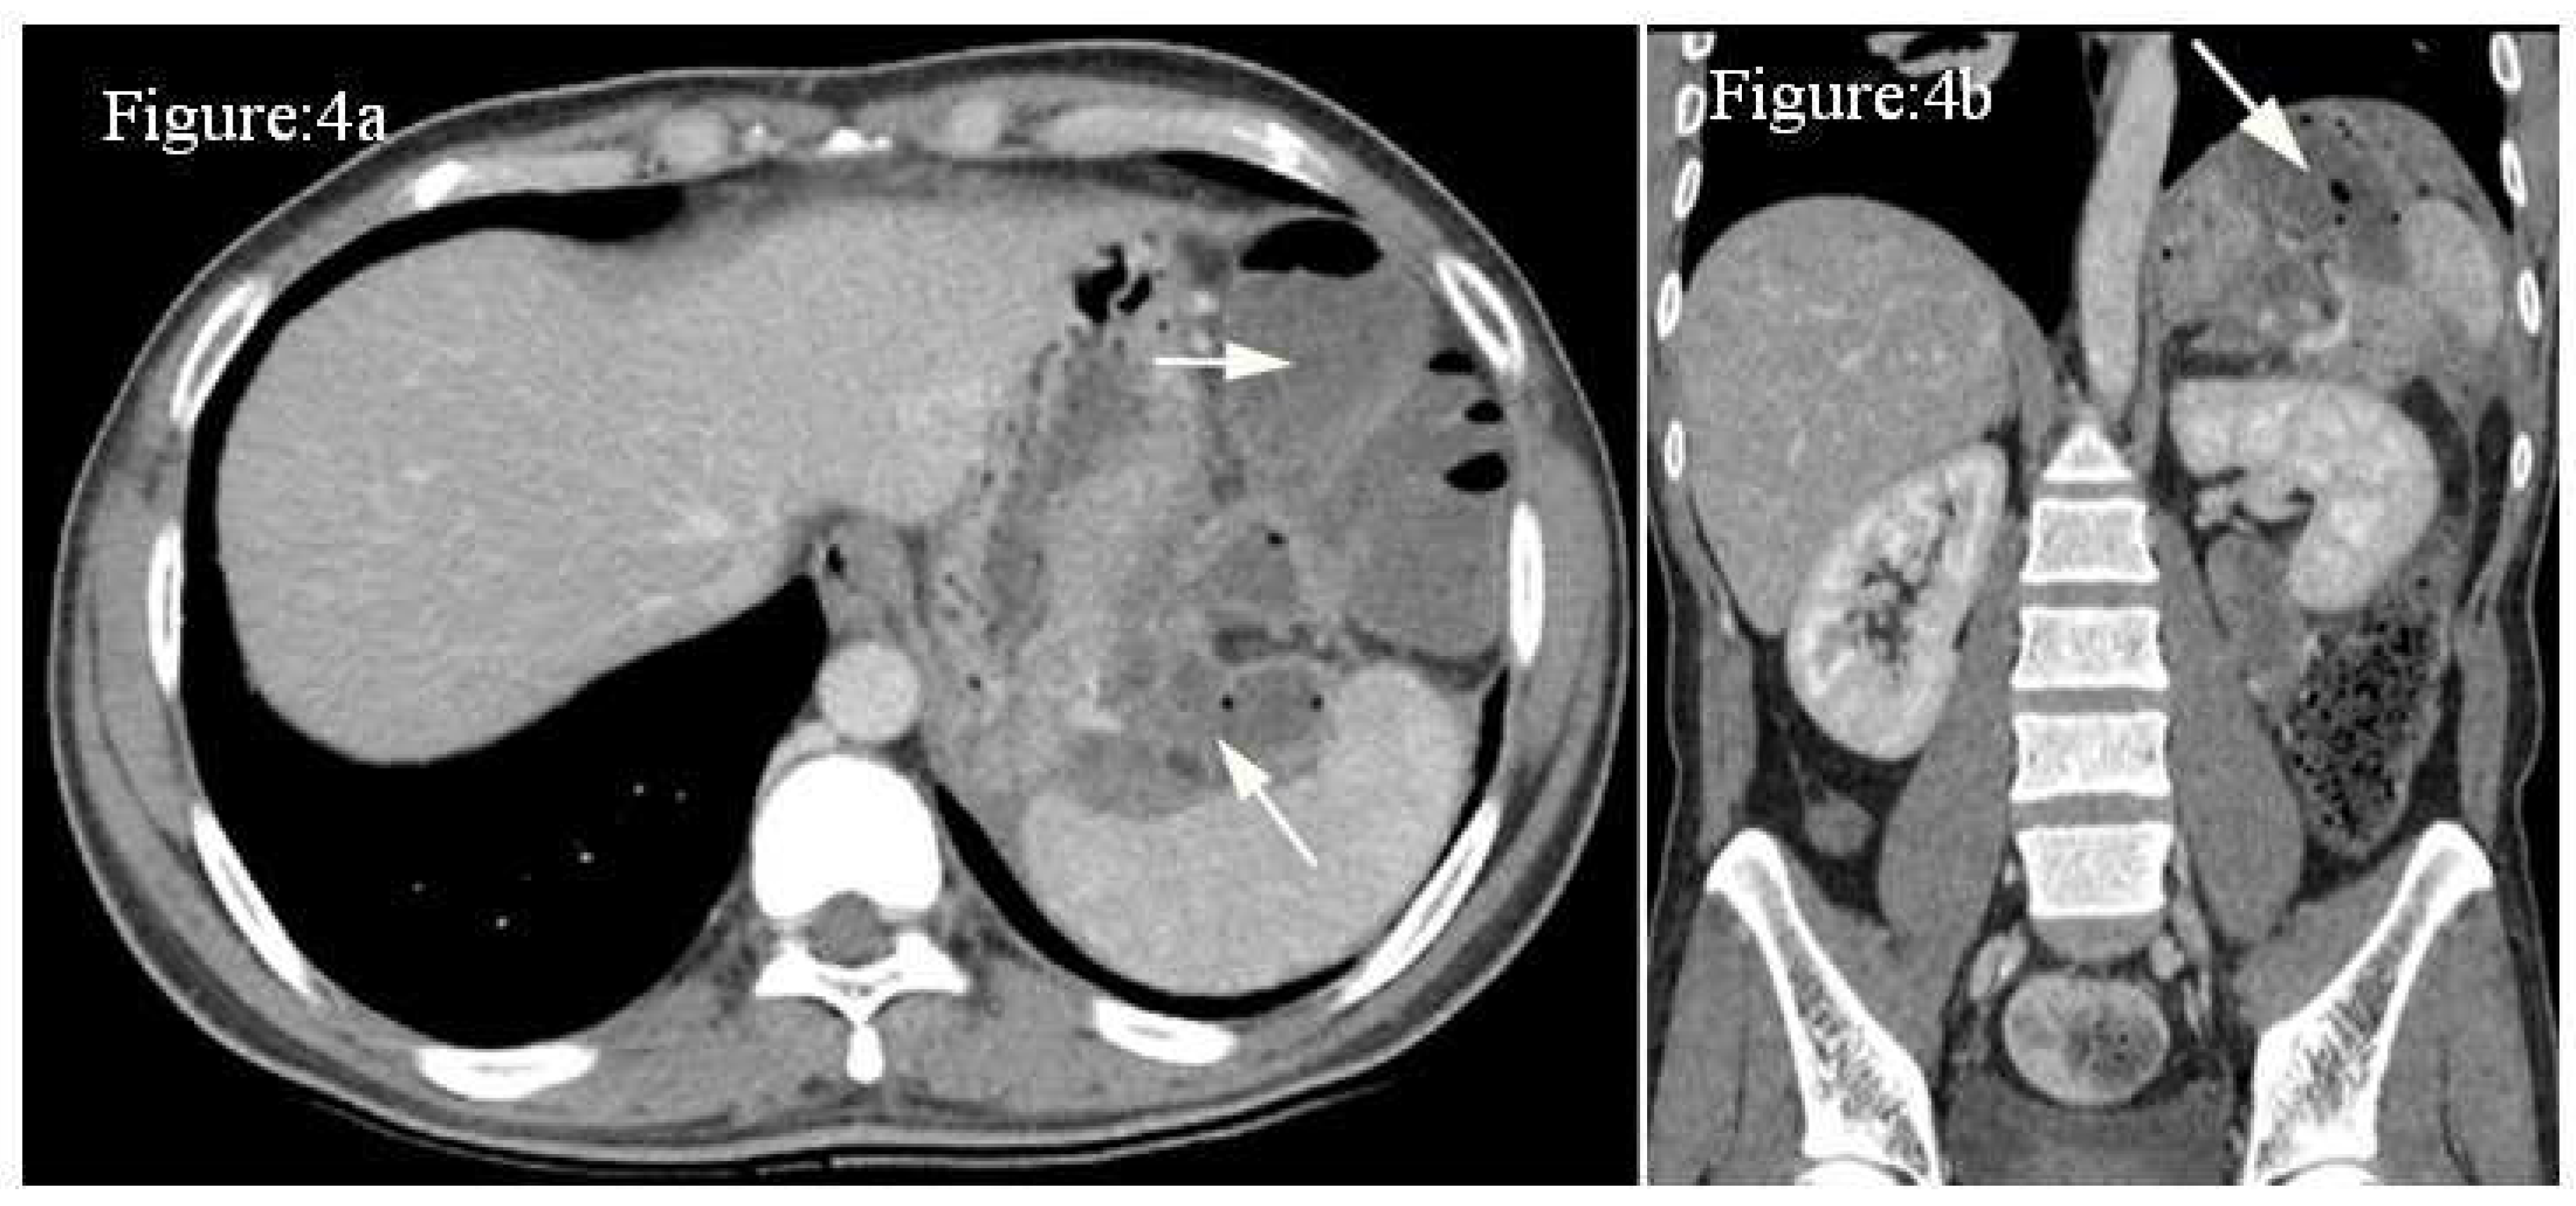

Case 4: